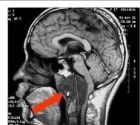

3.MRI腫瘤多為長T1長T2信號,瘤內囊變區呈更長T1長T2信號,鈣化為黑色無信號影,出血灶則呈高信號注射Gd-dtpa後腫瘤輕度至中度強化(圖1)。